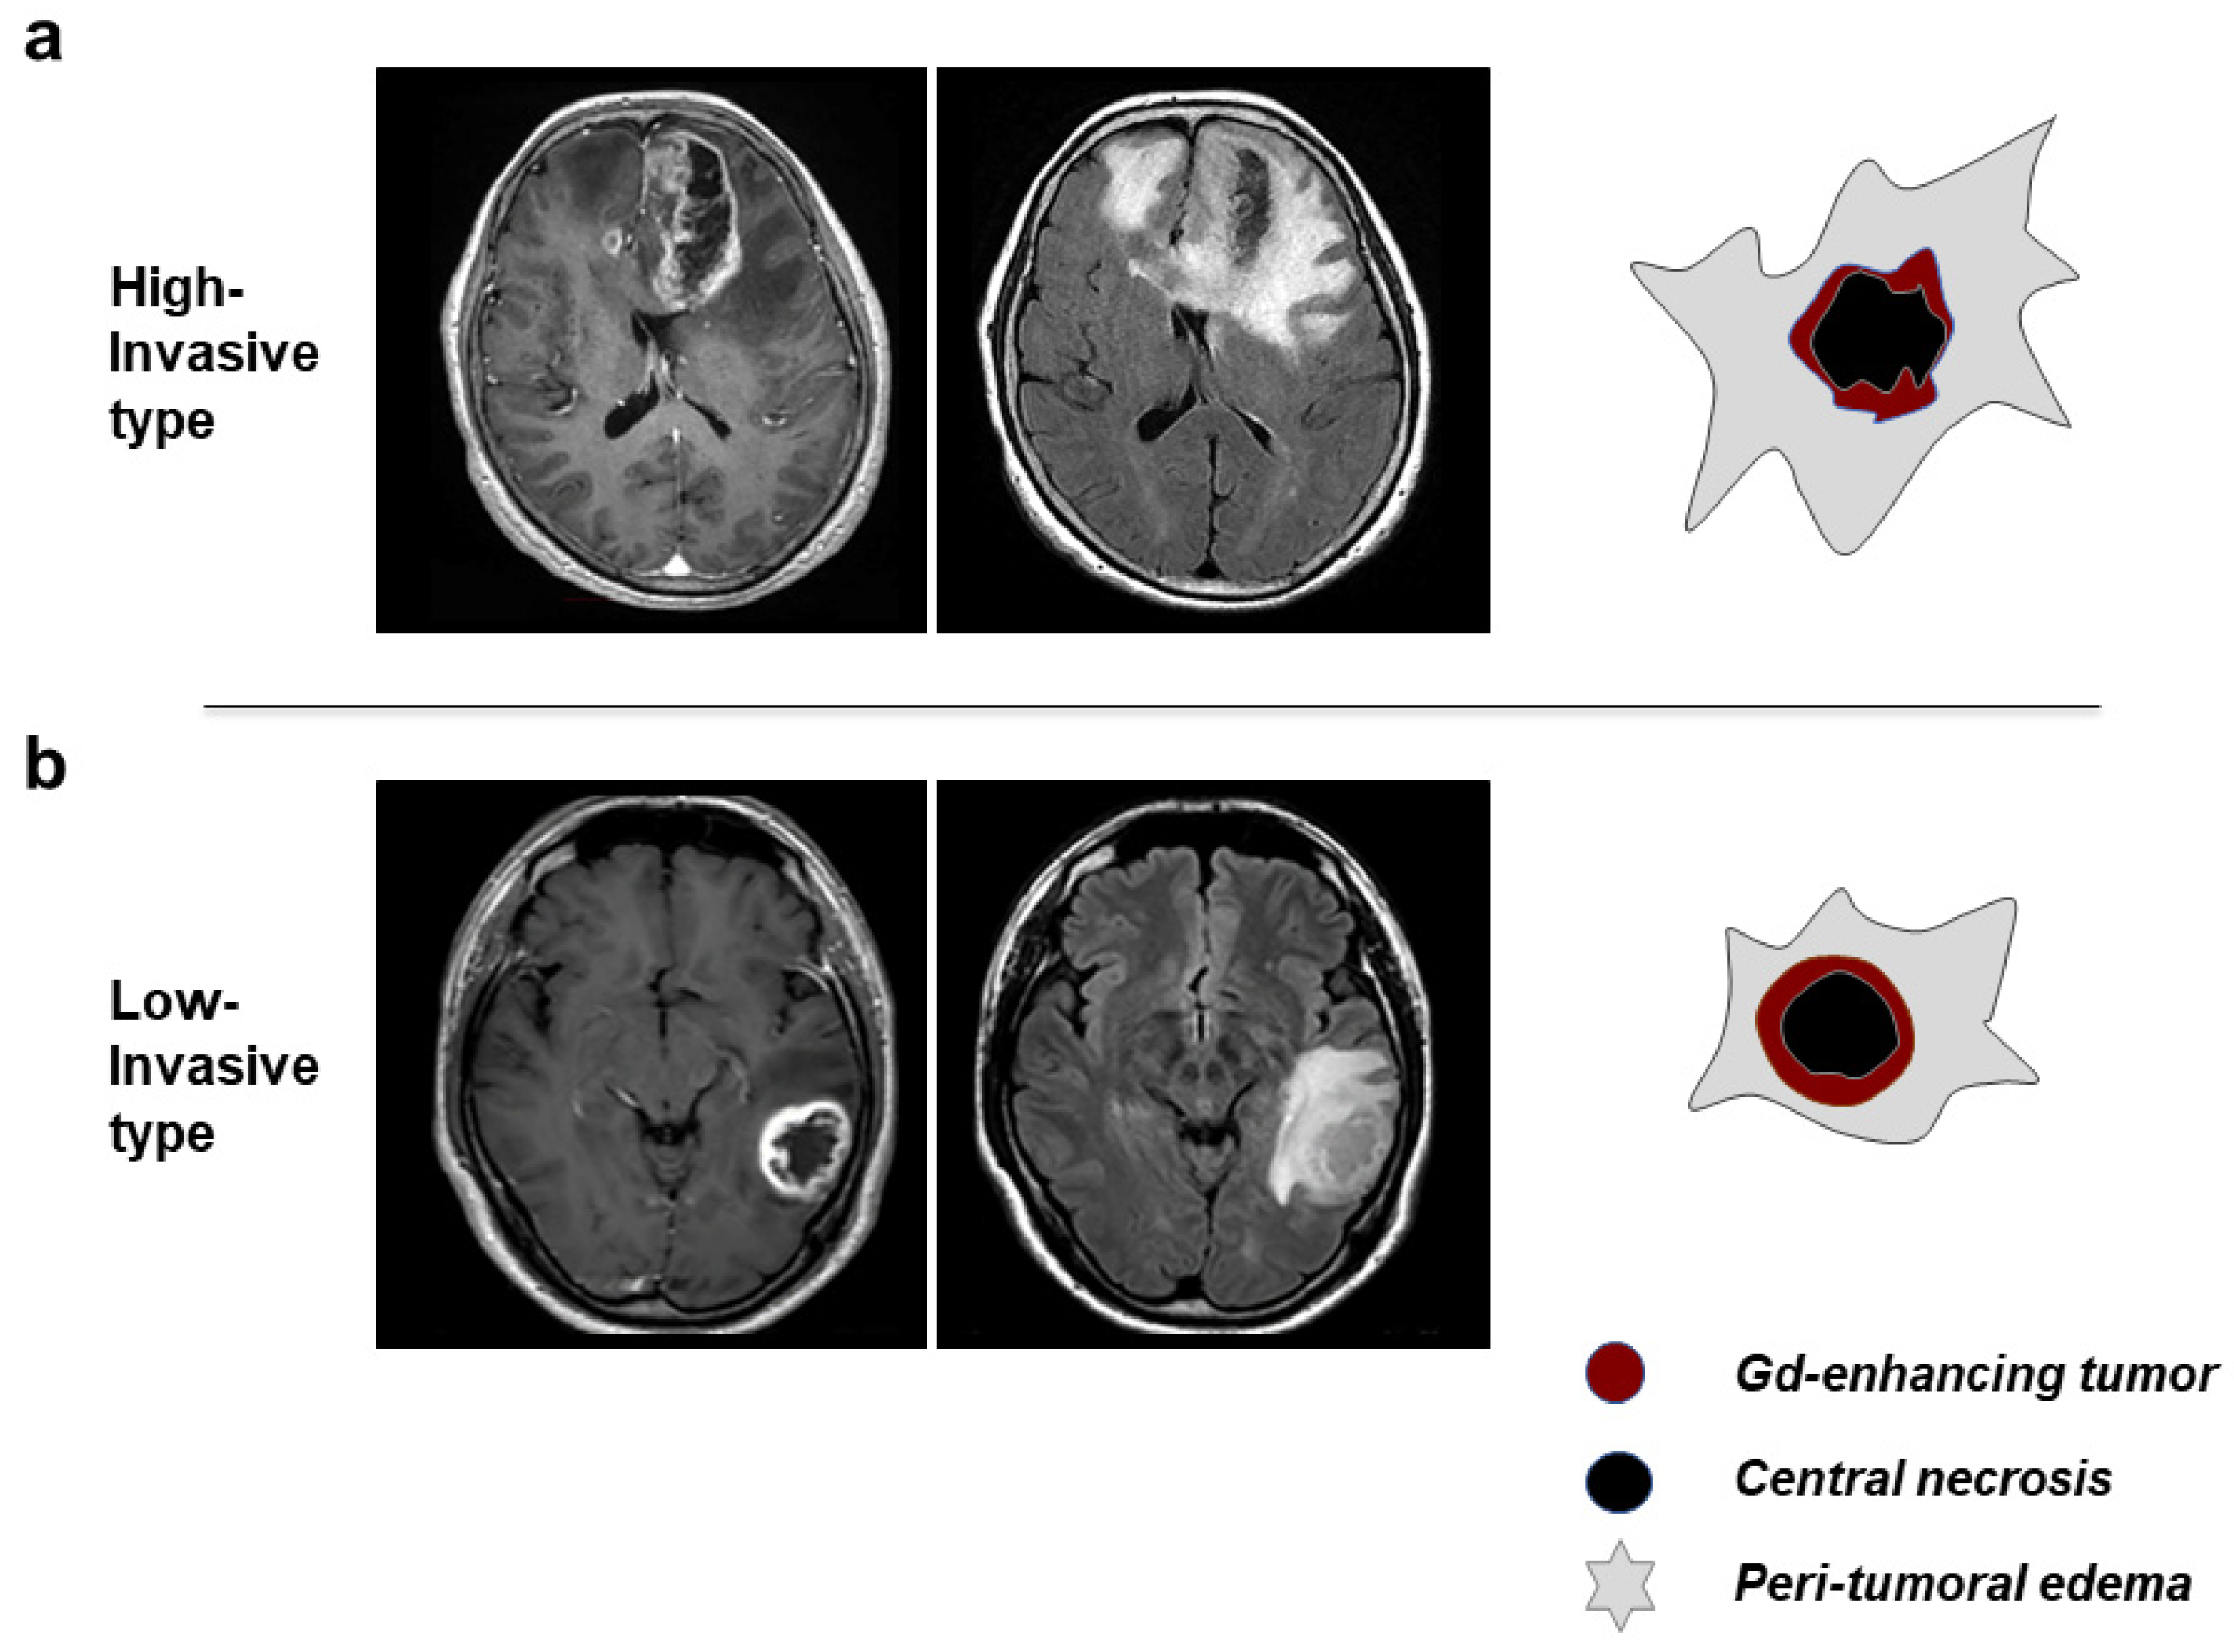

3.2. Classification of GBM Patients to HI and LI Types on MRI

| Features on MRI | High-Invasive Type | Low-Invasive Type |

| Morphology of tumor margin | irregular, thin wall | demarcated, thick wall |

| Enhancement of tumor margin wall | heterogeneous, weak-moderate | homogeneous, intense |

| Peritumoral brain edema | diffuse, extensive | focal, localized |

| Morphology of central necrosis | irregular, unevenly located | round, located at or near center |